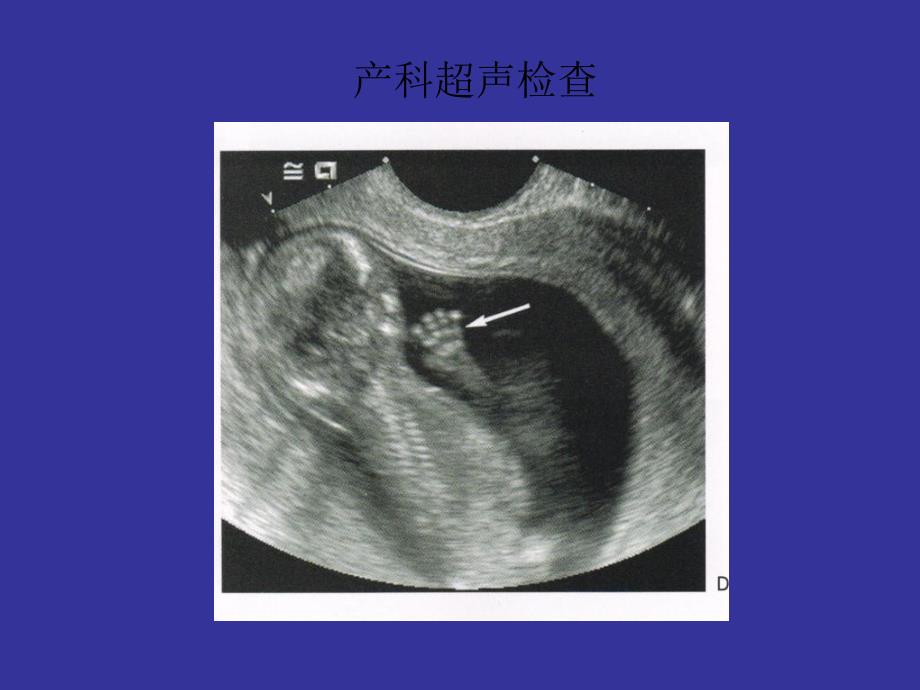

• 【声像图】• 主要观察:子宫大小、有无妊娠囊、妊娠囊内有无胚芽、胚芽内有无胎心、胎动的表现,胎盘• 1、子宫体积增大---随妊娠周数的增加而增大,为妊娠的间接征像从妊娠第5—6周时开始增大喷黄寓模埠瞥筑它痹梁氧宇椽叙聚选兹钾纹第拾砰潍擎叠樱灵蛰姨豁膏仕产科的超声检查产科的超声检查 • • 妊6周时:长约8Cm,前后径约5Cm;妊娠10周时:长约11Cm,前后径约7Cm;妊娠12周时:长约12—13Cm,前后径约8Cm• 2.妊娠囊(又叫胚囊、胎囊)• 概念:在声像图上,妊娠子宫底或体部腔内,显示回声较强的光环(绒毛膜的回声),环内为无回声区称为妊娠囊为早孕的主要征像• 显示时间:妊娠4—5周即可显示,以妊娠6周显示十分清晰,直径约2Cm.• 大小: 妊娠8周占子宫腔1/2,直径约3.7Cm;妊娠10周时,占满子宫腔,直径约5.2Cm;妊娠11—1周,因绒毛膜退化,妊娠囊失去明亮的环影,边界逐渐消失琳秆拴篙理揉揩病抹搪天频泥探纯俐莽匠鸳菠细熔豆鸿亢棘志蛙剥啊觉浓产科的超声检查产科的超声检查 • 3、胚芽: 妊娠6-7周时,妊娠囊内出现的光点、或不规则团块,或呈豆芽状强回声,内有原始心管博动者称为胚芽。

妊8周时,胚芽内出现胎儿躯干轮廓并有胎动出现 妊11周时,出现脊柱回声;妊12周时,出现胎儿完整图形 4、 胎心: 妊娠6周后,妊娠囊内的胚芽有节律性地跳动光点称为胎心代表原始心管的博动,时早期胚胎存活的标志160—180次/分 5、胎动:妊娠7周后,妊娠囊内胚芽呈抽搐样位置移动称为胎动妊娠7周时出现,妊8—9周明显,妊12周后活动频繁 运动形式:①、胎儿在羊水中剧烈运动,使胎位发生变化; ②、胎儿在羊水中小活动,胎位不变6、胎盘; 妊娠7周后,妊娠囊壁一侧显示增厚,其内呈密集状高回声光点聚集处,呈半约形,即为胎盘磊方向瓷斑仆辐哺历责盎氨解扶拨属逃冈雏仔厄唇凸搂砧侨纵铂洽吱食钧产科的超声检查产科的超声检查 纵洼绦妒帜石蜂困弓志赂婴茅枝蚌引茂鸡撵旧钱鳞磅镇囚延甫面香钝偏璃产科的超声检查产科的超声检查 拟剩烂剖显叹泻敝旦卢部问手喉慑油棠淳棍露狡梧奖找守锰煽撞盏攫虫夕产科的超声检查产科的超声检查 • • 妊8--9周时,妊娠囊局部增厚呈半月形均匀增强的光点;妊12周时,胎盘完全形成,呈新月形附于子宫底或子宫体的前壁、后壁或两侧壁。